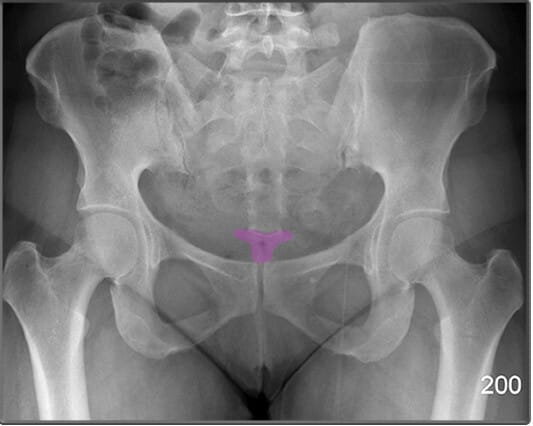

치골결합 (Pubic Symphysis)

| 치골결합 (Pubic Symphysis) |

| ✅ 치골의 정중앙에서 좌우를 연결하는 섬유연골 관절로, AP view에서 골반 중앙 하단에서 좁은 간격의 음영으로 보입니다. |

| 🔴 외상이나 분만 후 이완이나 분리(pubic diastasis)가 발생할 수 있습니다. |

치골결절 (Pubic Tuberosity)

| 치골결절 (Pubic Tuberosity) |

| ✅ 치골의 상단에서 약간 돌출된 부위로, AP view 에서는 치골결합 바로 옆에서 작고 밀도 높은 음영으로 보입니다. |

| 🔴 인대 부착 부위로 해부학적 기준점으로 활용됩니다. |

상치골지 (Superior Pubic Ramus)

| 상치골지 (Superior Pubic Ramus) |

| ✅ 치골의 상단 분지로, 치골결합에서 대각선으로 위쪽으로 뻗어 장골과 연결됩니다. AP View에서는 골반 앞쪽 상부에서 연속적인 골 음영으로 나타납니다. |

| 🔴골반 고리의 안정성을 평가하는데 중요한 구조입니다. |

하치골지 (Inferior Pubic Ramus)

| 하치골지 (Inferior Pubic Ramus) |

| ✅ 치골의 하부 분지로, 좌골과 연결되어 골반 하부를 구성합니다. AP view에서 치골결합 아래쪽에서 대각선 방향으로 연장된 음영으로 나타납니다. |

| 🔴 외상성 골절이 흔히 발생하는 부위입니다. |